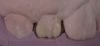

A 16-year-old female patient presented with the chief complaint that she was dissatisfied with the appearance of her anomalous maxillary lateral incisors (teeth Nos. 7 and 10) and multiple diastemas (Figure 1 through Figure 4). She had been referred for restorative treatment after an initial consultation with the orthodontist. Her first restorative appointment was dedicated to data collection, which included a health history and physical examination as well as the acquisition of photographs (facial, dentofacial, dental), videos (chief complaint, F sound, S sound), vinyl polysiloxane (VPS) impressions, a panoramic radiograph, a bite registration, and a facebow registration. The clinical examination revealed that both of the patient's maxillary lateral incisors were peg-shaped. After a discussion about the risks and benefits of different treatment options, such as direct composite restoration, indirect composite veneers, and porcelain laminate veneers, she chose to have her maxillary lateral incisors treated with direct composite buildup restorations. The index cutback technique was chosen for this case instead of a freehand technique in order to create a new shape according to an ideal wax-up but also to be able to control the thickness of the enamel layer.7

The rubber dam was removed from the mouth, and the excess material was removed with a No. 12B scalpel blade and a fine diamond bur. Next, the light-reflecting and light-deflecting zones were verified with a pencil and adjusted with finishing burs.11 The occlusion was then verified statically and dynamically using articulating paper and adjusted as needed. After finishing, the immediate postoperative polishing process was accomplished with a series of polishing discs followed by the use of a buffing disc with a diamond polishing paste (Figure 30). Eight days later, the patient returned to the office, and the final polishing was accomplished with polishing discs and diamond polishing paste (Figure 31 through Figure 35).

An assessment of the shape and shade of the final restorations was performed. It was noted that the incisal edges of the restored lateral incisors were not as white as those of the central incisors. Rather than adding additional stain to the lateral incisors, the patient expressed her desire to have some of the white staining removed from the central incisors using a resin infiltration technique after her orthodontic treatment. The final orthodontic treatment for the maxillary arch would involve closing the spaces in the anterior area, protracting the posterior teeth, and finishing in a Class II relationship. For the mandibular arch, the goal would only be to maintain the current positions of the teeth.